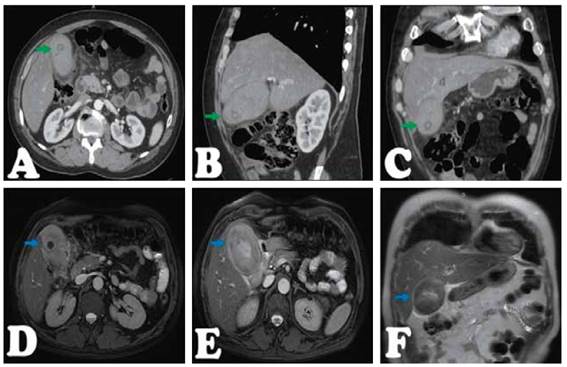

Presentamos el caso de un varón de 57 años, con antecedente de TBC pulmonar hace 20 años. Que hace 2 días presentó dolor en CSD, con irradiación a zona lumbar ipsilateral, asociado a náuseas y vómitos, y orinas oscuras. Por lo que acude a hospital, donde le realizan una ecografía abdominal, informada como VB con formación tumoral (Figura 1A), siendo referido a nuestro hospital. A su ingreso por emergencia, persistía el dolor en CSD a pesar de medicación analgésica. Al examen, paciente hemodinámicamente estable, dolor y masa palpable en CSD, y signo de Murphy positivo. La analítica de ingreso mostró una hemoblogina 14.0(VN:12-16gr/dl), hemograma 13000(VN: 5000-10000/mm3), INR 1.17, Bilirrubina total de 7.06 (a predominio directo 1.45) (VN:0.2-1.2mg/dl), fosfatasa alcalina(FA): 170(VN:27-100U/L), Gama-glutamil transferasa (GGTP): 409(VN:12-45U/L), amilasa en 66(VN: 0-120U/L), TGO 850(VN:<45U/L), TGP 980(VN:<45U/L). La ecografía fue informada como signos de CA litiásica con contenido biliar denso (Figura 1B). Se realizó una TC abdominal informada como CA litiásica con cambios inflamatorios perivesiculares y contenido hiperdenso, a considerar barro biliar o hemorragia (Figura 2A, 2B y 2C). Los marcadores tumorales (CA 125, AFP, CA19.9, CEA) y serológicos resultaron negativos; y los controles de hemoglobina y bilirrubinas disminuyeron de 14 a 12gr/dl y 7.06 a 0.66 respectivamente; además gastroenterología descartó proceso tumoral ampular. Finalmente, la colangioresonancia concluyó signos de CA litiásica con bilis de señal hemática (Figura 2D,2E y 2F). Por lo que se decide su intervención quirúrgica, realizándose una colecistectomía laparoscópica, donde se evidenció adherencias de epiplón, colon transverso, duodeno y VB, una VB gangrenada en cuerpo y bacinete conteniendo coágulos rojo oscuro y múltiples litiasis ( ). Paciente cursa con buena evolución, recibiendo antibióticoterapia y tres dosis de ácido tranexámico. Tolera dieta oral a las 8 horas de la cirugía, y dieta blanda a las 24 horas, y es dado de alta a los 2 días, tolerando dieta y sin drenajes. El estudio histopatológico reveló áreas de hemorragia, necrosis e infiltrado inflamatorio agudo, confirmando el diagnóstico ( ).

Figura 2 Tomografía abdominal con contraste. Vesícula distendida de 106x60mm paredes al parecer gruesas (poco definibles) contenido hiperdenso >60UH, que con el contraste varía muy poco, presenta litiasis internas con densidades mixtas y cambios inflamatorios periféricos. Flecha verde, A, Corte transversal. B, Corte sagital. C, Corte coronal. Colangioresonancia con contraste. Vesícula distendida de 98x59mm paredes engrosadas e irregulares, contenido de señal baja(hipointensa) heterogénea en T2, alta heterogénea en FIESTA, que contiene litiasis en el fondo de 15mm, y finas colecciones perivesiculares. Flecha azul, D y E, Corte transversal. F, Corte coronal.